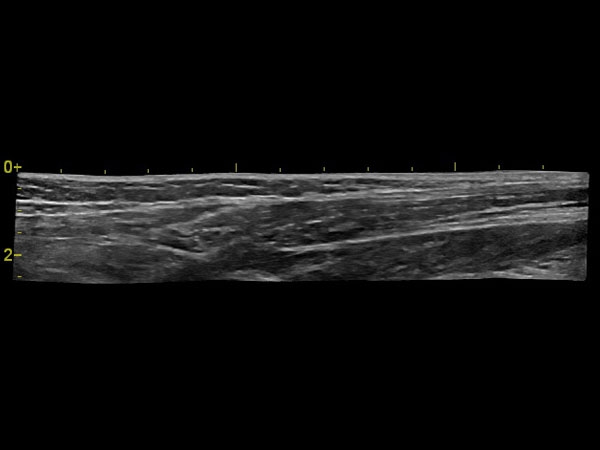

Панорамное сканирование:

Да

• Линейный датчик GE L6-12-RS

• Линейный датчик GE 9L-RS

• Линейный датчик GE 12L-RS